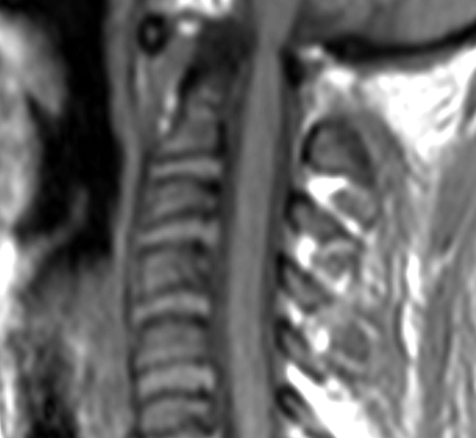

三、关节脱位

MRI诊断:

分为完全脱位和部分脱位。前者表现为组成关节诸骨的对应关系完全脱离或分离;后者表现为相对应的关节面失去正常关系,关节面分离、移位、关节间隙宽窄不均(图8)。可伴有关节骨、软骨损伤,关节囊内可见积液。MRI还有助于发现关节内碎片,脱位关节周围韧带、肌腱损伤。

图8 关节半脱位矢状位T1WI示寰椎前弓与枢椎齿突间距增宽,约5.5mm。